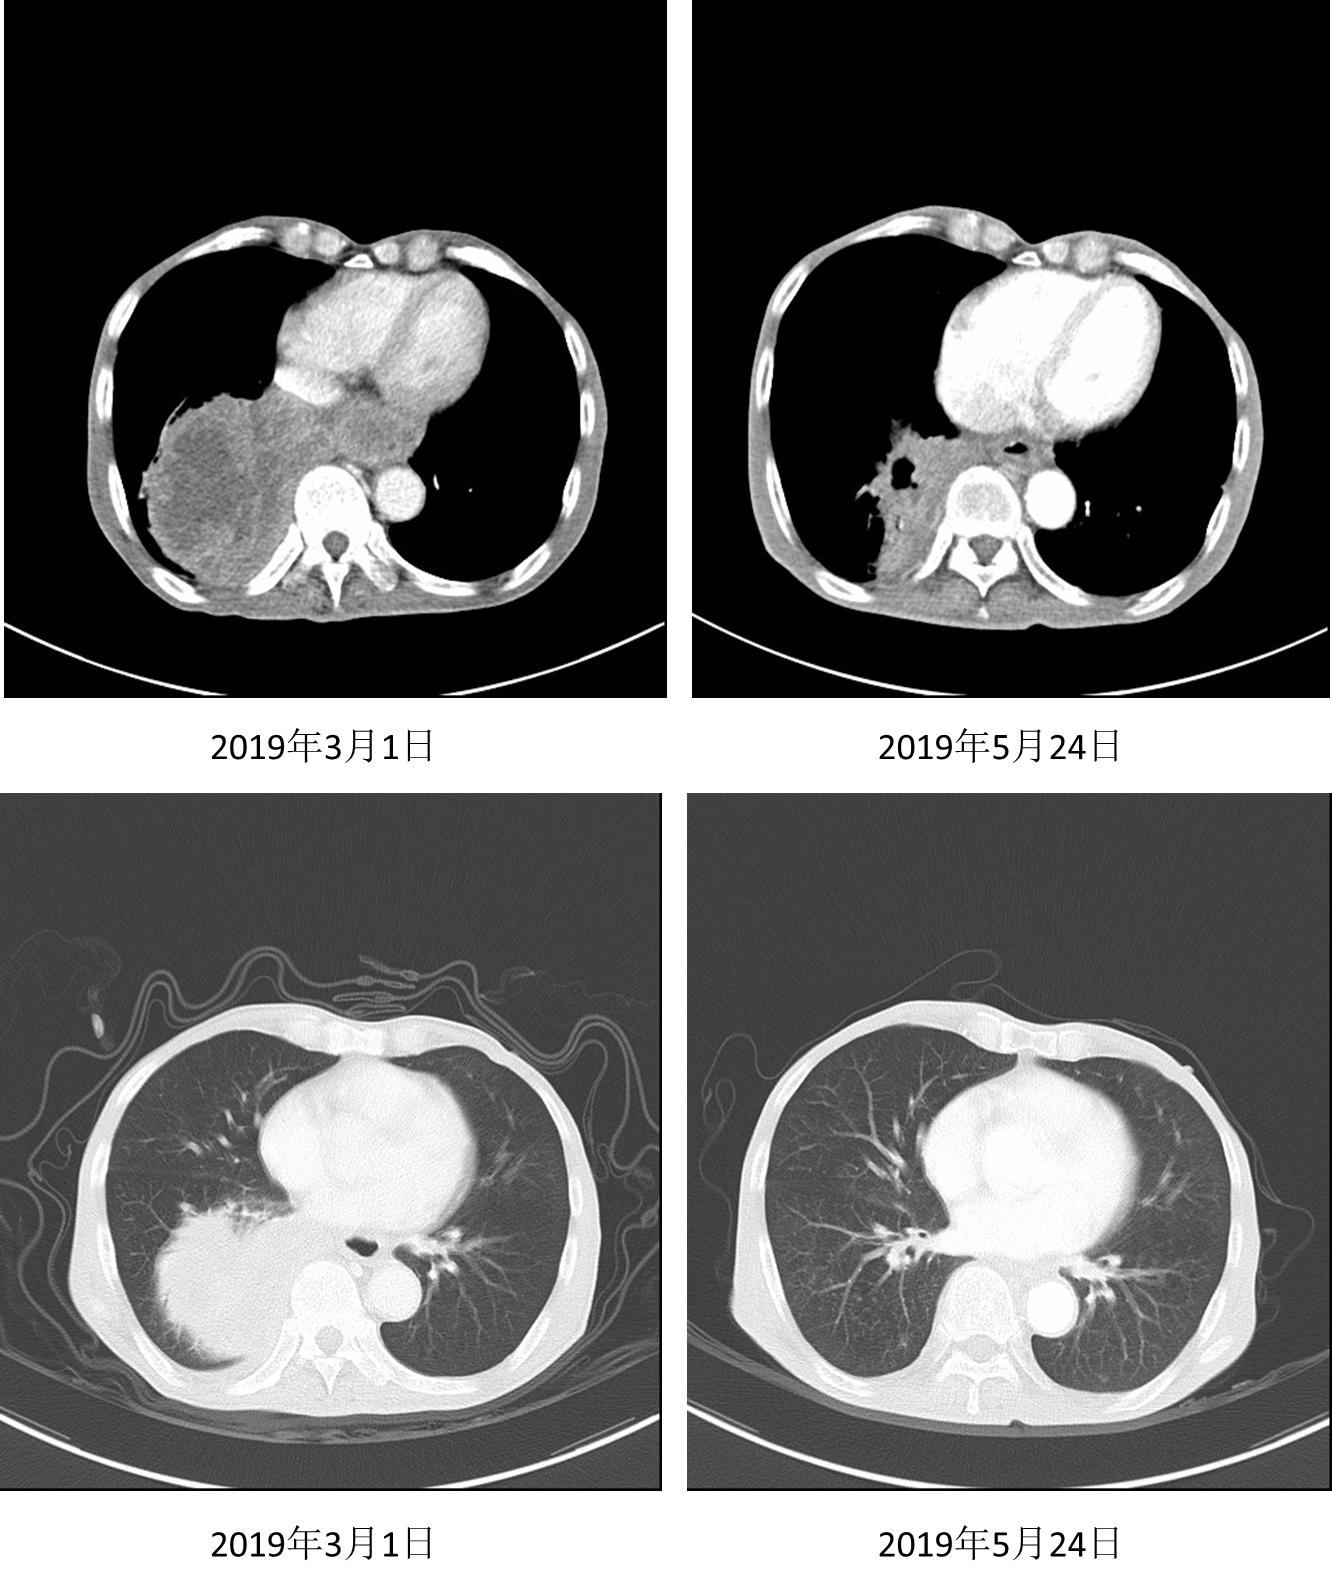

三线治疗

在沟通疗效和价格等因素后,患者自行选择信迪利单抗。2019年4月3日、4月30日、5月21日行信迪利单抗200mg D1治疗3个周期,患者症状缓解(自诉从“躺在床上”到“早上逛菜市场”)。2019年5月24日复查胸部CT示:右肺下叶软组织肿块影范围较前明显缩小,强化不均,范围约77mm *50mm。

图4. 2019年5月24日复查

2019年6月12日、7月2日继续行信迪利单抗200mg D1治疗2周期。2019年8月14日继续随访CT,结果示右肺下叶软组织肿块影范围较前明显缩小,强化不均,范围约28mm * 20mm,邻近胸膜增厚。疗效评价为部分缓解(PR),接近完全缓解(CR)。